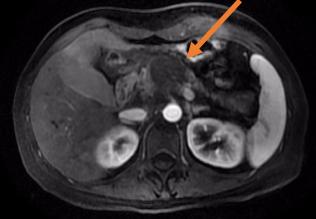

海扶刀在医学影像引导下,将体外低强度超声波聚焦于体内病灶,如同长了眼睛一般精准定位肿瘤。继而形成高能量的焦点,瞬态的高温(60℃—100℃)让肿瘤迅速凝固性坏死,而肿瘤以外组织却不受到明显损伤。通过控制焦点的三维组合运动,海扶刀以“点-束-片-块的”方式最终完成对整块靶组织的适形消融治疗。也就是说,海扶刀能“隔空打穴”,无需开刀,不会出血,通过超声波精准消灭肿瘤。

一位胰腺癌患者初诊时已是晚期,无根治性手术指征,来到青大附院就诊。传统治疗模式是以化疗为主,联合止痛、营养治疗。由于患者营养状态较差,治疗前评估其对化疗的耐受较差。在治疗肿瘤和担心副作用之间,患者和家属无数次徘徊和犹豫。海扶治疗为患者提供了一种新选择。肿瘤内科主任于壮组织会诊,制定详细方案,在麻醉科的配合下,于宁主任为患者完成全麻下胰腺病灶超声消融。手术后复查,该患者胰腺病灶“完美”消融,疼痛逐渐消失,恢复进食,体力状态较治疗前明显好转。接下来,患者在肿瘤内科接受了化疗,有足够的营养状态做支撑,没有出现严重的化疗相关副反应,肿瘤得到了长期的控制,生活质量也得到了极大改善。

胰腺癌被称为“癌中之王”,虽然发病率不高,但死亡率很高。患者初次诊断时大多已经发展为局部晚期或出现转移,失去手术机会。海扶刀治疗给胰腺癌患者带来多方面的改善。一是能快速缓解疼痛。九成伴有疼痛的患者通过一次治疗就能够有效缓解疼痛,明显改善生活质量。二是快速让肿瘤坏死,再联合化疗、放疗等其他治疗方式,大大延长患者生存时间和质量。近3年的研究结果显示,局部晚期(尚未转移)胰腺癌患者应用上述联合方式治疗后平均生存时间已超过2年。“癌中之王”尚且能被遏制,海扶刀对恶性肿瘤治疗效果可管窥一豹。